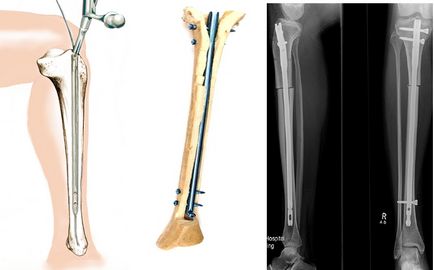

Javítás Az alsó végtag tengellyel, amikor varus deformitás tüskékkel (csapok)

Csontösszekötő rudak (csapok)

Ez a technika a legkisebb terjedését, összehasonlítva a másik két (lemezek és eszközök). A látszólagos előnye az a stabil rögzítés, amely lehetővé teszi, hogy működtetni egyszer mindkét végtag és rendelkezik egy korai funkciója és oporosposbnost. A módszer lényege abban áll, hogy amikor az előre dörzsárazás a medulláris csatornába a femorális vagy a tibia pin abban beépített megfelelő átmérőjű.

A rendszer a beadás, a helyzetét a csap a csonton belül a műtét után, és röntgenfelvételek

Annak ellenére, hogy a csapok be egy kis bemetszést, lehetetlen, hogy ezt a kíméletes módszer. Fennáll a veszélye a súlyos szövődmények. Ha, például, amikor a Ilizarov külső rögzítőszerkezet, gyulladás vagy tályog a helyi, felületes és könnyen gyógyítható, majd az intramedulláris tályog azzal fenyeget, hogy elterjedt az egész folyamat a medulláris csatornába. Ez is nagyon nehéz elérni szimmetrikus korrekciós mindkét láb, ami nagyon fontos a kozmetikai sebészet.

Tekintettel a súlyos szövődmények, nem szeretnénk ajánlani ezt a technikát, amikor esztétikai láb alakja korrekciója. Van hasznosságát csap nyúlása hosszú távú rögzítőszerkezeteken a Ilizarov jelentősen csökkenti az életminőséget a betegek.